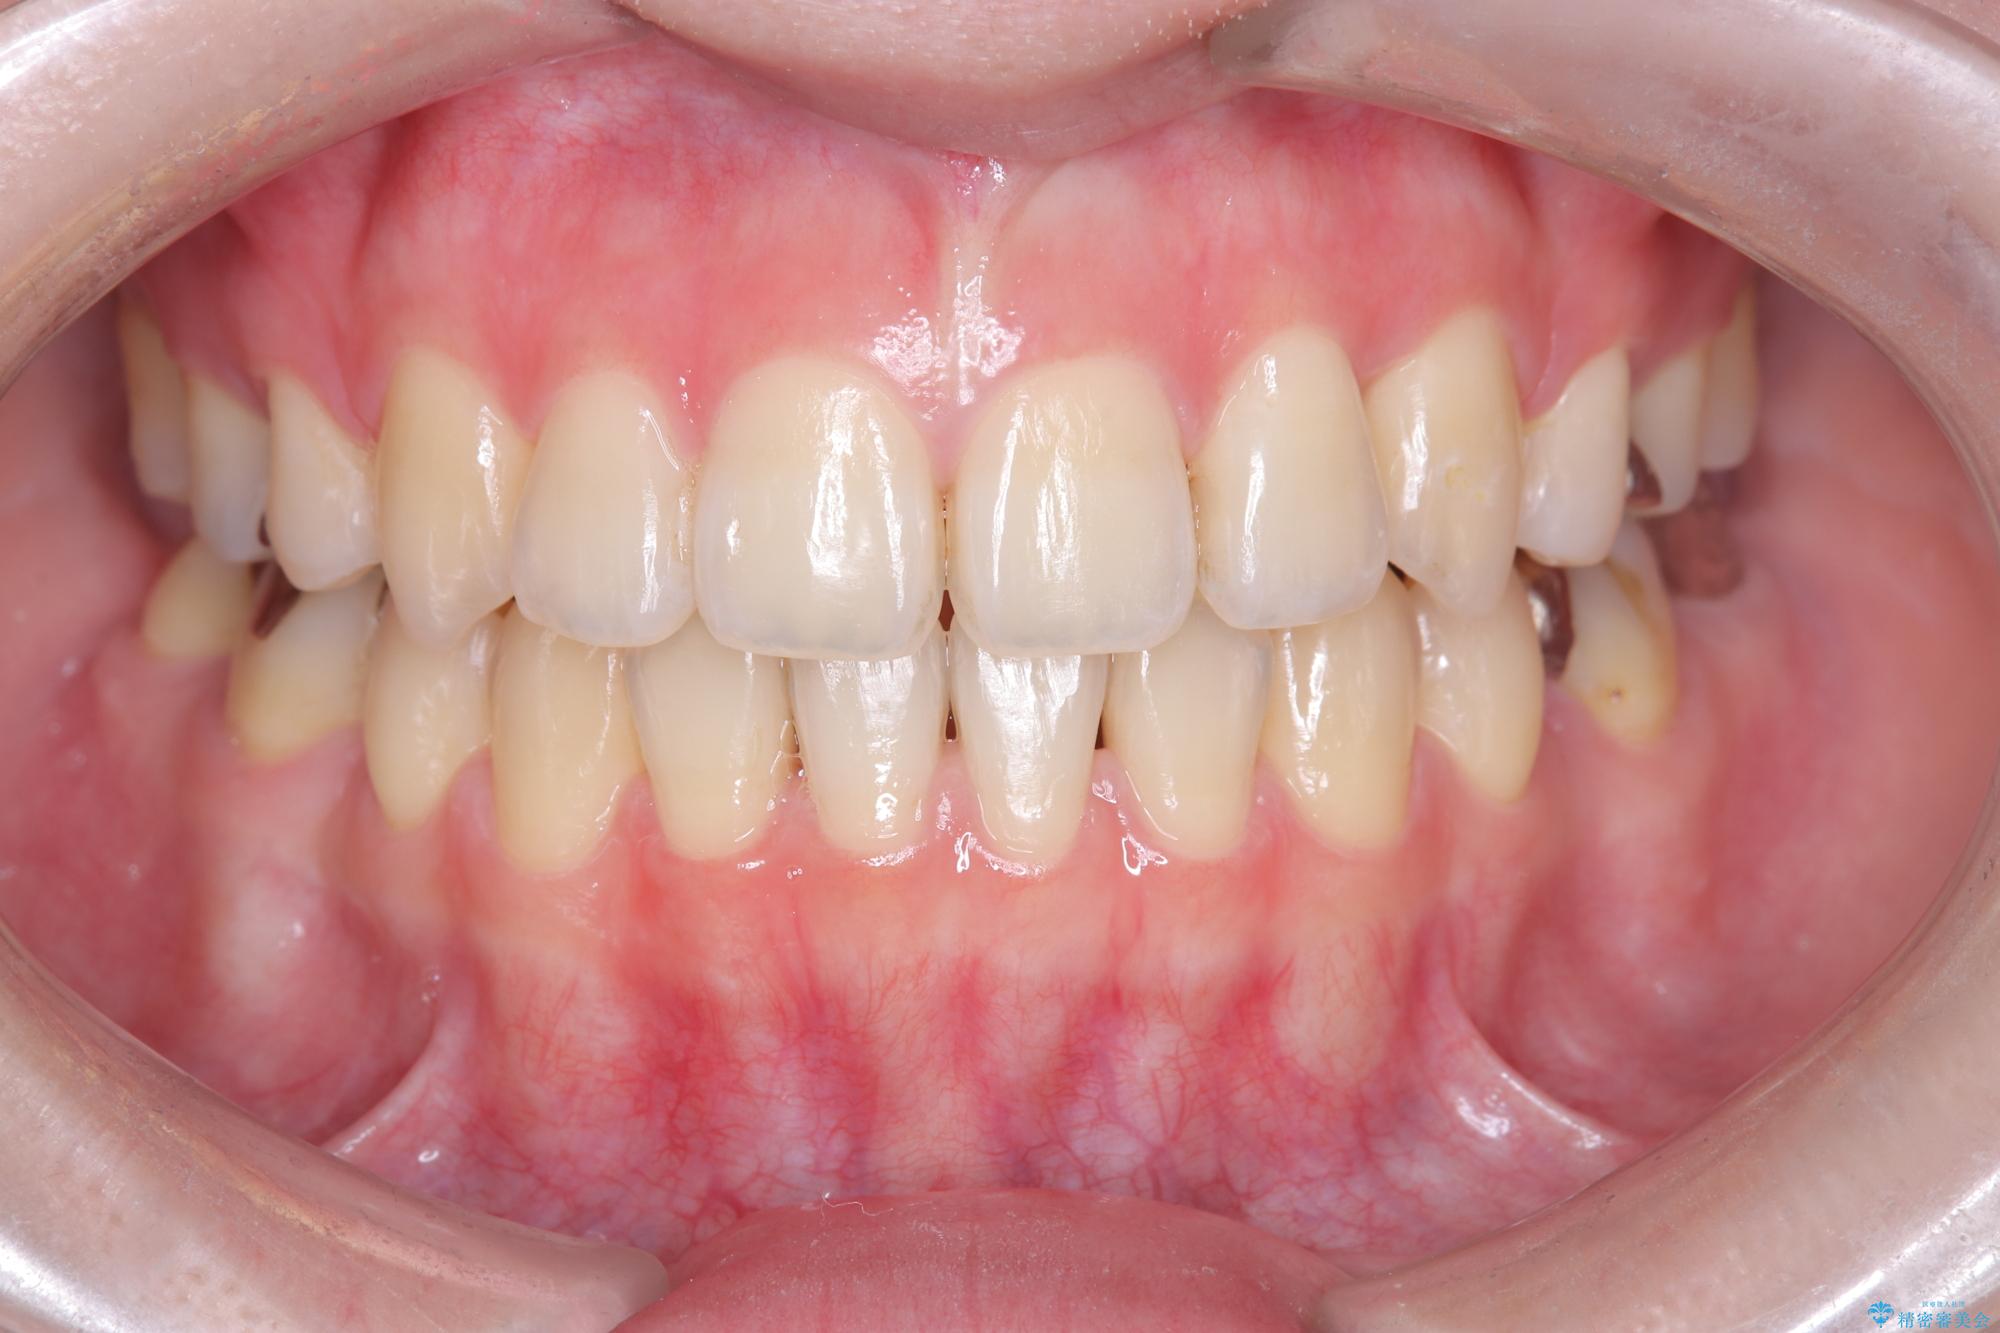

開咬や歯列のデコボコが改善され、見た目だけでなく咬み合わせの機能面も大きく向上し、大変ご満足いただけました。

また、治療期間も比較的短期間で終了することができました。